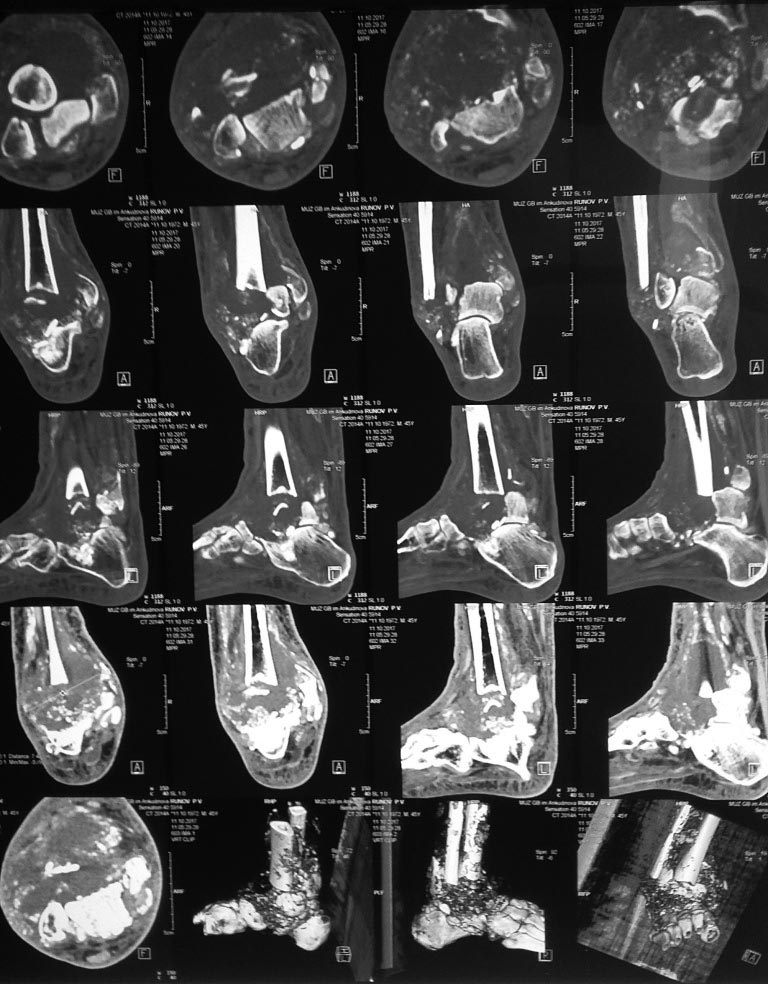

помогите разобраться. непонятный больной...

факт травмы, оперативного лечения пациент отрицает. со слов 2 недели назад появился отёк и патологическая подвижность в голеностопном суставе. у пациента сахарный диабет 1 типа. резкое снижение чувствительности в нижних конечностях. боли нет... сегодня при пункции "сустава" получен серозно-геморрагический пунктат светло-розового цвета.

стопа Шарко, не?!

Стопа шарко. Костыли!!! Лечение диабета, время... месяцев 4—5

Это стопа Шарко!